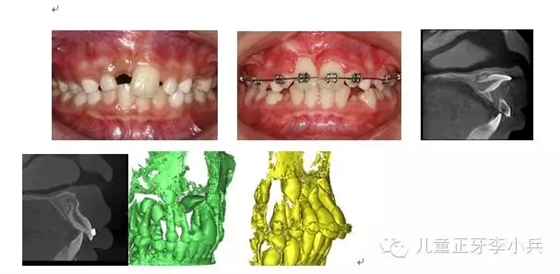

2. 彎根牙的早期牽引助萌:先天及乳牙外傷導致繼承恒牙牙冠及牙根發(fā)育異常,臨床出現(xiàn)牙冠發(fā)育不全及彎根牙。彎根牙的牽引助萌常受到彎根嚴重程度及彎根角度的影響,早期牽引能引導牙根形成方向,降低牙根彎曲的嚴重程度。(圖3,彎根牙的早期牽引治療)

圖 3 11彎根牙的早期牽引,11牙根繼續(xù)發(fā)育,牙根彎曲程度減?。?